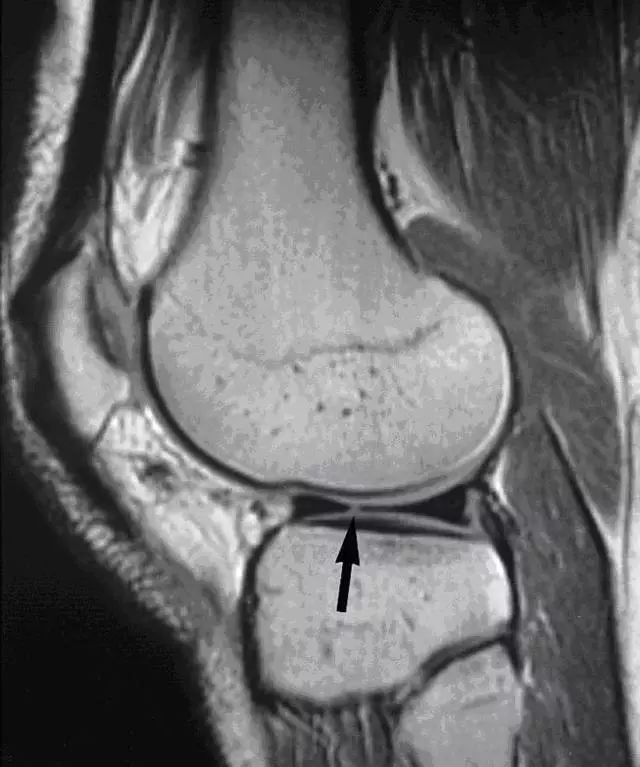

图 9 矢状面图像上可看到黑色箭头所指处,有一线性增强信号横贯内侧半月板后角,提示半月板斜行撕裂。